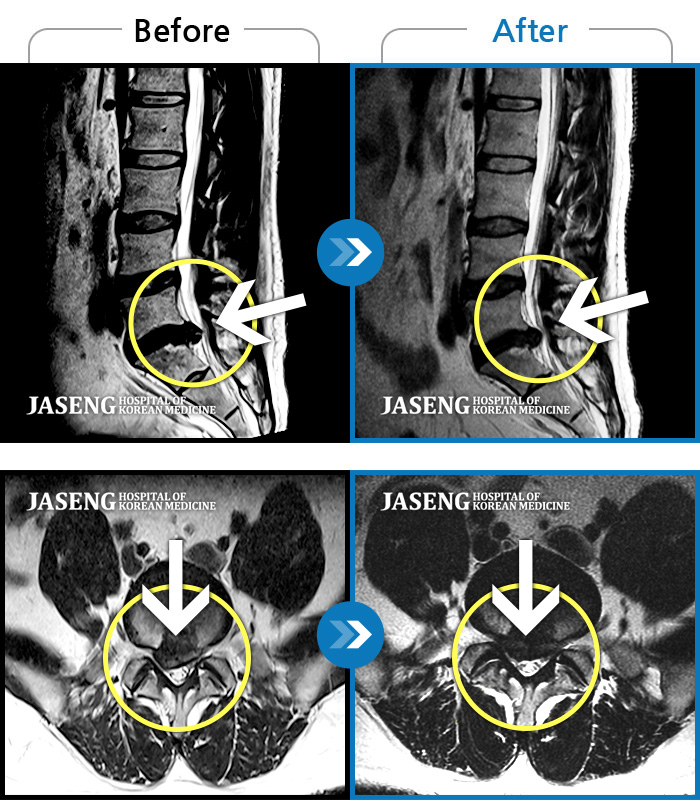

처음 내원 시 허리와 좌측 골반이 많이 아프고, 좌측 다리로 저림과 감각 저하가 있어서 보행이 원활하지 못했으며, 야간통으로 잠도 못 자고 통증 심하여 정상적인 활동이 힘든 상태셨습니다.

2023.09.16 ~ 2024.09.24